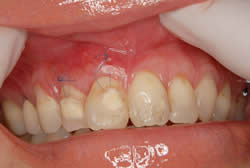

症例230代 女性 主訴 右上犬歯の歯が長いのが気になる。

治療前

治療後

説明 主訴 右上犬歯の歯が長いのが気になるとのことで来院。根面被覆(Root coverage)口蓋(上顎)から歯肉を採取し、露出している根面に歯肉を移植し被覆。

露出が目立たなくなり、歯肉のラインもきれいに改善された。

リスクとしては、外科的侵襲がある。デメリットは、保険外診療の為、経済的負担がある。

費用 11万(税込)(歯肉移植)